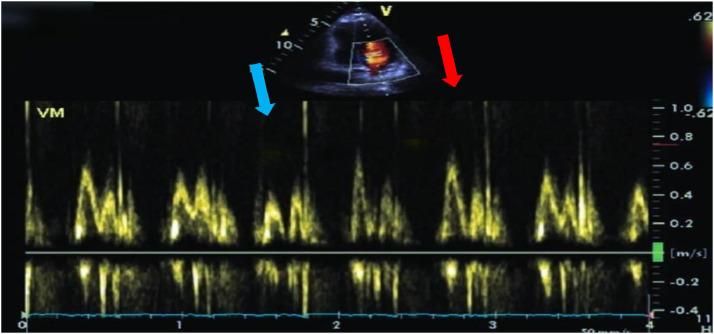

Chronic constrictive pericarditis is a pericardial affection that causes a severe impairment of myocardial compliance. Among its many etiologies, tuberculosis is the most common cause, mainly in developing countries. Multimodal imaging methods are essential tools for guiding diagnosis. We present the case of a 64-year-old man with no past medical history who presented with dyspnea stage II of NYHA and right heart failure. At admission, he was stable, with normal blood pressure and a normal heart rate. His ECG showed a low voltage of QRS complexes. Transthoracic echocardiography revealed significant pericardial thickening enveloping the ventricles, with significant respiratory flow variation. A thoracic CT scan and cardiac MRI confirmed the presence of pericardial thickening and calcifications. The patient underwent beat-heart pericardial decortication. The anatomopathological examination of the surgical piece revealed Mycobacterium tuberculosis. The postoperative check-up after 6 months showed good clinical and echocardiographic evolution.

慢性缩窄性心包炎是一种导致心肌顺应性严重受损的心包疾病。在其众多病因中,结核病是最常见的病因,主要发生在发展中国家。多模态成像方法是指导诊断的重要工具。我们报告一例64岁男性患者,既往无病史,出现纽约心脏协会(NYHA)II级呼吸困难和右心衰竭。入院时,他病情稳定,血压正常,心率正常。他的心电图显示QRS波群低电压。经胸超声心动图显示心室周围心包显著增厚,伴有显著的呼吸血流变化。胸部CT扫描和心脏磁共振成像证实存在心包增厚和钙化。患者接受了心脏不停跳心包剥脱术。手术标本的解剖病理学检查发现结核分枝杆菌。6个月后的术后检查显示临床和超声心动图有良好的进展。